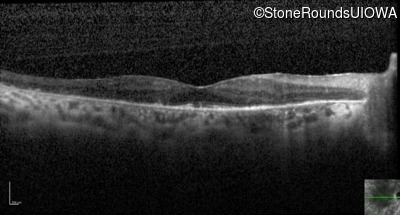

Optical Coherence Tomography - Right - 20/25

Exemplar / OCT Stack